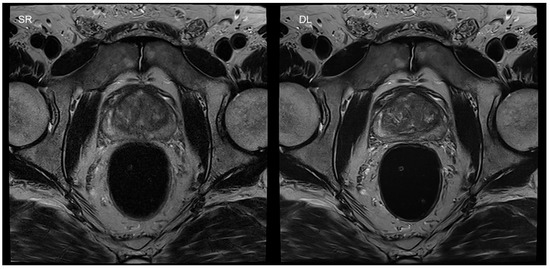

- Gassenmaier, S.; Afat, S.; Nickel, D.; Mostapha, M.; Herrmann, J.; Othman, A.E. Deep learning-accelerated T2-weighted imaging of the prostate: Reduction of acquisition time and improvement of image quality. Eur. J. Radiol. 2021, 137, 109600. [Google Scholar] [CrossRef] [PubMed]

- Gassenmaier, S.; Afat, S.; Nickel, M.D.; Mostapha, M.; Herrmann, J.; Almansour, H.; Nikolaou, K.; Othman, A.E. Accelerated T2-Weighted TSE Imaging of the Prostate Using Deep Learning Image Reconstruction: A Prospective Comparison with Standard T2-Weighted TSE Imaging. Cancers 2021, 13, 3593. [Google Scholar] [CrossRef]